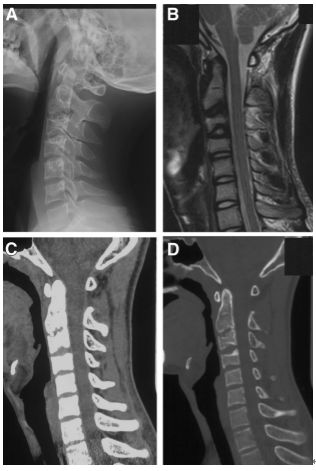

图:患者8岁,女孩,因严重颈部疼痛、活动受限伴左上肢无力、麻木不适2天就诊。既往有锁骨骨折、额部软组织挫伤病史。查体:颈椎活动受限,左上肢肌力正常,但感觉减退。白细胞、血沉、CRP升高。颈椎侧位片和CT平扫提示C6-7椎间盘钙化(粗箭头)和后纵韧带骨化(细箭头),颈椎MRI提示C6-7水平脊髓明显受压。给予颈椎制动、枕颌带2.5kg颈椎牵引2周。随后,颈托固定1个月。2年后随访复查颈椎CT如下图,同时上述症状完全缓解。

图:2年后复查CT示C6-7钙化的椎间盘和后纵韧带骨化都消失了